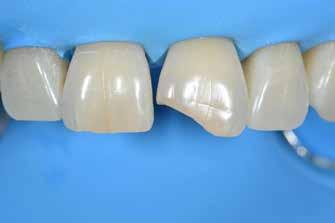

Nem volt kedvencem, de kevésbé kedveltem a hibrid technikát, ahol a palatális fal wax-uppal történő felépítése, majd a nyaki terület szabadkézi megerősítése után a restauráció többi részét mátrixszal lehetett kivitelezni (1. ábra). Bár a kezemben ez valahogy hatékony volt, mégis bonyolult volt.

1. ábra: A wax-up alapú technikák gyakori problémái, a szájpadlásfal apikális része hibás.

A szabadkézi technikák legnagyobb problémája kétségtelenül a nyaki pontosság hiánya és a túlnyúlások létrehozása. Számtalan olyan pácienst láttam, akiknek vérző ínyük volt, és nem tudtak megfelelően fogselymet használni. A másik gyakori probléma a klasszikus megközelítéssel kapcsolatban a végső forma volt. A dupla kiemelkedő profil miatt a végleges restaurációnak kellemetlen alakja volt (2-4. ábra). A kizárólag mátrixokkal történő közvetlen diasztémazárás problémái a nyaki szinten a túlkontúrozás és az alulkontúrozás, a diszkordáns kontaktpontok, az eltolt proximális kontaktok és a masszív többlettermelés. Hogy őszinte legyek, engem mindig is lebeszéltek arról, hogy ezzel a megközelítéssel próbálkozzam.

2-4. ábra: Gyakori problémák klasszikus megközelítéssel. 5. ábra: Tökéletes vészhelyzeti profil elülső szárnyas technikával. Dr. Jun Iwata, Japán jóvoltából.